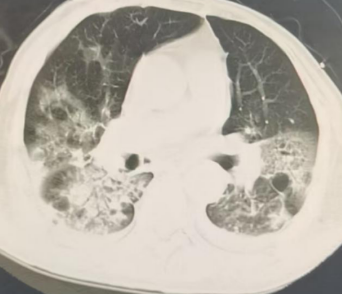

2025-10-28复查胸部CT:气管插管术后,气管腔内可见高密度影附着。桶状胸廓,双肺可见多发类圆形无壁及薄壁透光区,双肺内可见散在斑片状稍高密度影,边缘模糊不清,部分实变。双侧胸腔内可见弧形液体密度影,右侧为著。主动脉及冠状动脉走行区可见致密影。双侧胸腔内未见积液。